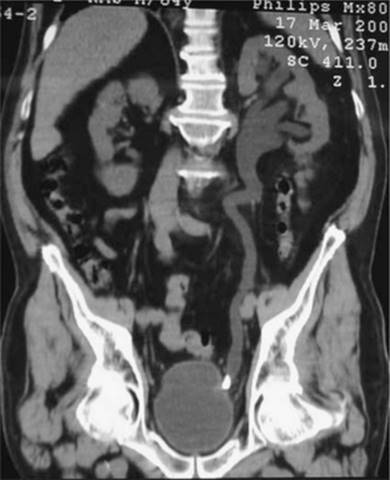

Prior to the popularity of CT for diagnosis, which has the advantages of high sensitivity, speed, lack of contrast administration and ability to detect other intra-abdominal pathologies, intravenous urography (IVP) was used to confirm the diagnosis of urinary obstruction, with demonstration of the causative calculus, either as a radio-opaque shadow in line with the ureter or as a radiolucent filling defect (Figs 9.4a-c), or showing a dilated upper urinary tract as the aftermath of a stone that has passed. IVP is now rarely performed in most emergency departments but is a useful adjunct if the diagnosis is equivocal. Ultrasound can be helpful in excluding other intra-abdominal and pelvic lesions or to demonstrate and serially monitor upper urinary tract dilatation due to obstruction. Ultrasound is thus of particular value in children, in whom repeated X-rays should be avoided. Renal colic with symptoms and signs of pyelonephritis (fever, systemic toxicity) always requires urgent imaging. An obstructed and infected kidney requires urgent relief, whereas obstruction in the absence of infection can be observed over the course of a week or more without likelihood of renal parenchymal damage.

Figure 9.4a Ureteric stone

Right-sided obstruction from stone causing hydronephrosis.

Figure 9.4b CT stone coronal view of VUJ stone

Reproduced with permission from John Kourambas

Figure 9.4c IVP demonstrating proximal ureteric stone